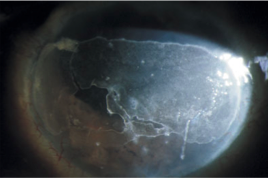

Describa la siguiente imagen

Catarata Morganiana